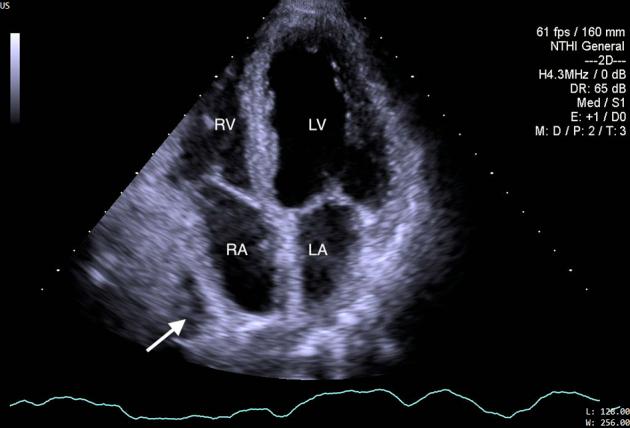

A Case of Hepatic Cyst-Induced Internal Jugular Venous Thrombosis.

• Echocardiography can demonstrate hepatic cyst–induced right atrial compression. • Hepatic cyst–induced blood flow stasis can cause internal jugular venous thrombus. • Laparoscopic deroofing of hepatic cysts is a safe and effective treatment.

• 超声心动图可显示肝囊肿所致的右心房受压。